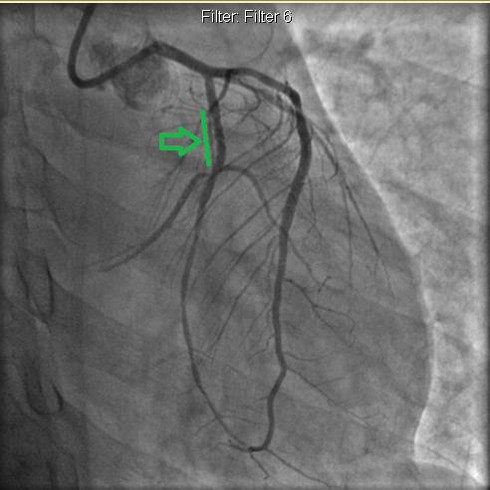

Hình ảnh chụp mạch vành sau khi được đặt 1 stent trên LCX1 và tái lưu thông tốt.Ảnh BVCC |

Các bác sĩ nghi ngờ viêm cơ tim nhưng trên nền men tim tăng nhanh. Các yếu tố cũng như kết quả siêu âm đều hướng về nhồi máu cơ tim. Ngay lập tức bệnh nhân được chụp mạch vành. Kết quả chụp mạch vành là nhánh mũ tắc hoàn toàn.

Triệu chứng đau ngực của bệnh nhân thuyên giảm ngay sau khi được can thiệp. Ngoài ra, BN tươi tỉnh hơn, bớt khó thở, ăn uống khá hơn và cử động được nhẹ nhàng trên giường. Xét nghiệm troponin giảm dần. Siêu âm tim kiểm tra thấy sức co bóp các thành cơ tim có cải thiện. Sau 5 ngày, bệnh nhân được ra viện kèm lời dặn uống thuốc mỗi ngày theo toa và khám hằng tháng tại chuyên khoa tim mạch.

Theo bác sĩ Ngô Võ Ngọc Hương - Khoa Tim mạch tổng quát, Bệnh viện Nhân dân 115 trường hợp của anh L. là một bài học lâm sàng đáng lưu ý về nhồi máu cấp ở người trẻ và đòi hỏi thái độ tích cực tái lưu thông mạch vành sớm.